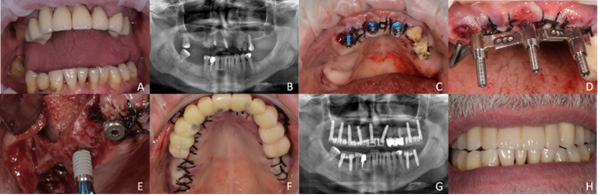

Complications were observed in 8 patients (22.86%), corresponding to 8.64% (n = 19) of delivered implants. All complications except one occurred in the implants placed in allogenic bone. Specifically, non-early osseointegration involved 3 implants (1.36%), radiographic radiolucency – 8 implants (3.64%), peri-implantitis – 4 implants (1.82%), and implant mobility – 1 implant (0.45%). Moreover, 1 implant delivered to a non-smoking patient was lost after 57 months due to peri-implantitis. Another patient with previous chronic periodontitis, recurrent bleeding and a significant muscular strength/chewing force, lost 2 implants after 115 months. Figure 1 and Figure 2 show 2 different cases which were successfully rehabilitated with the proposed technique.